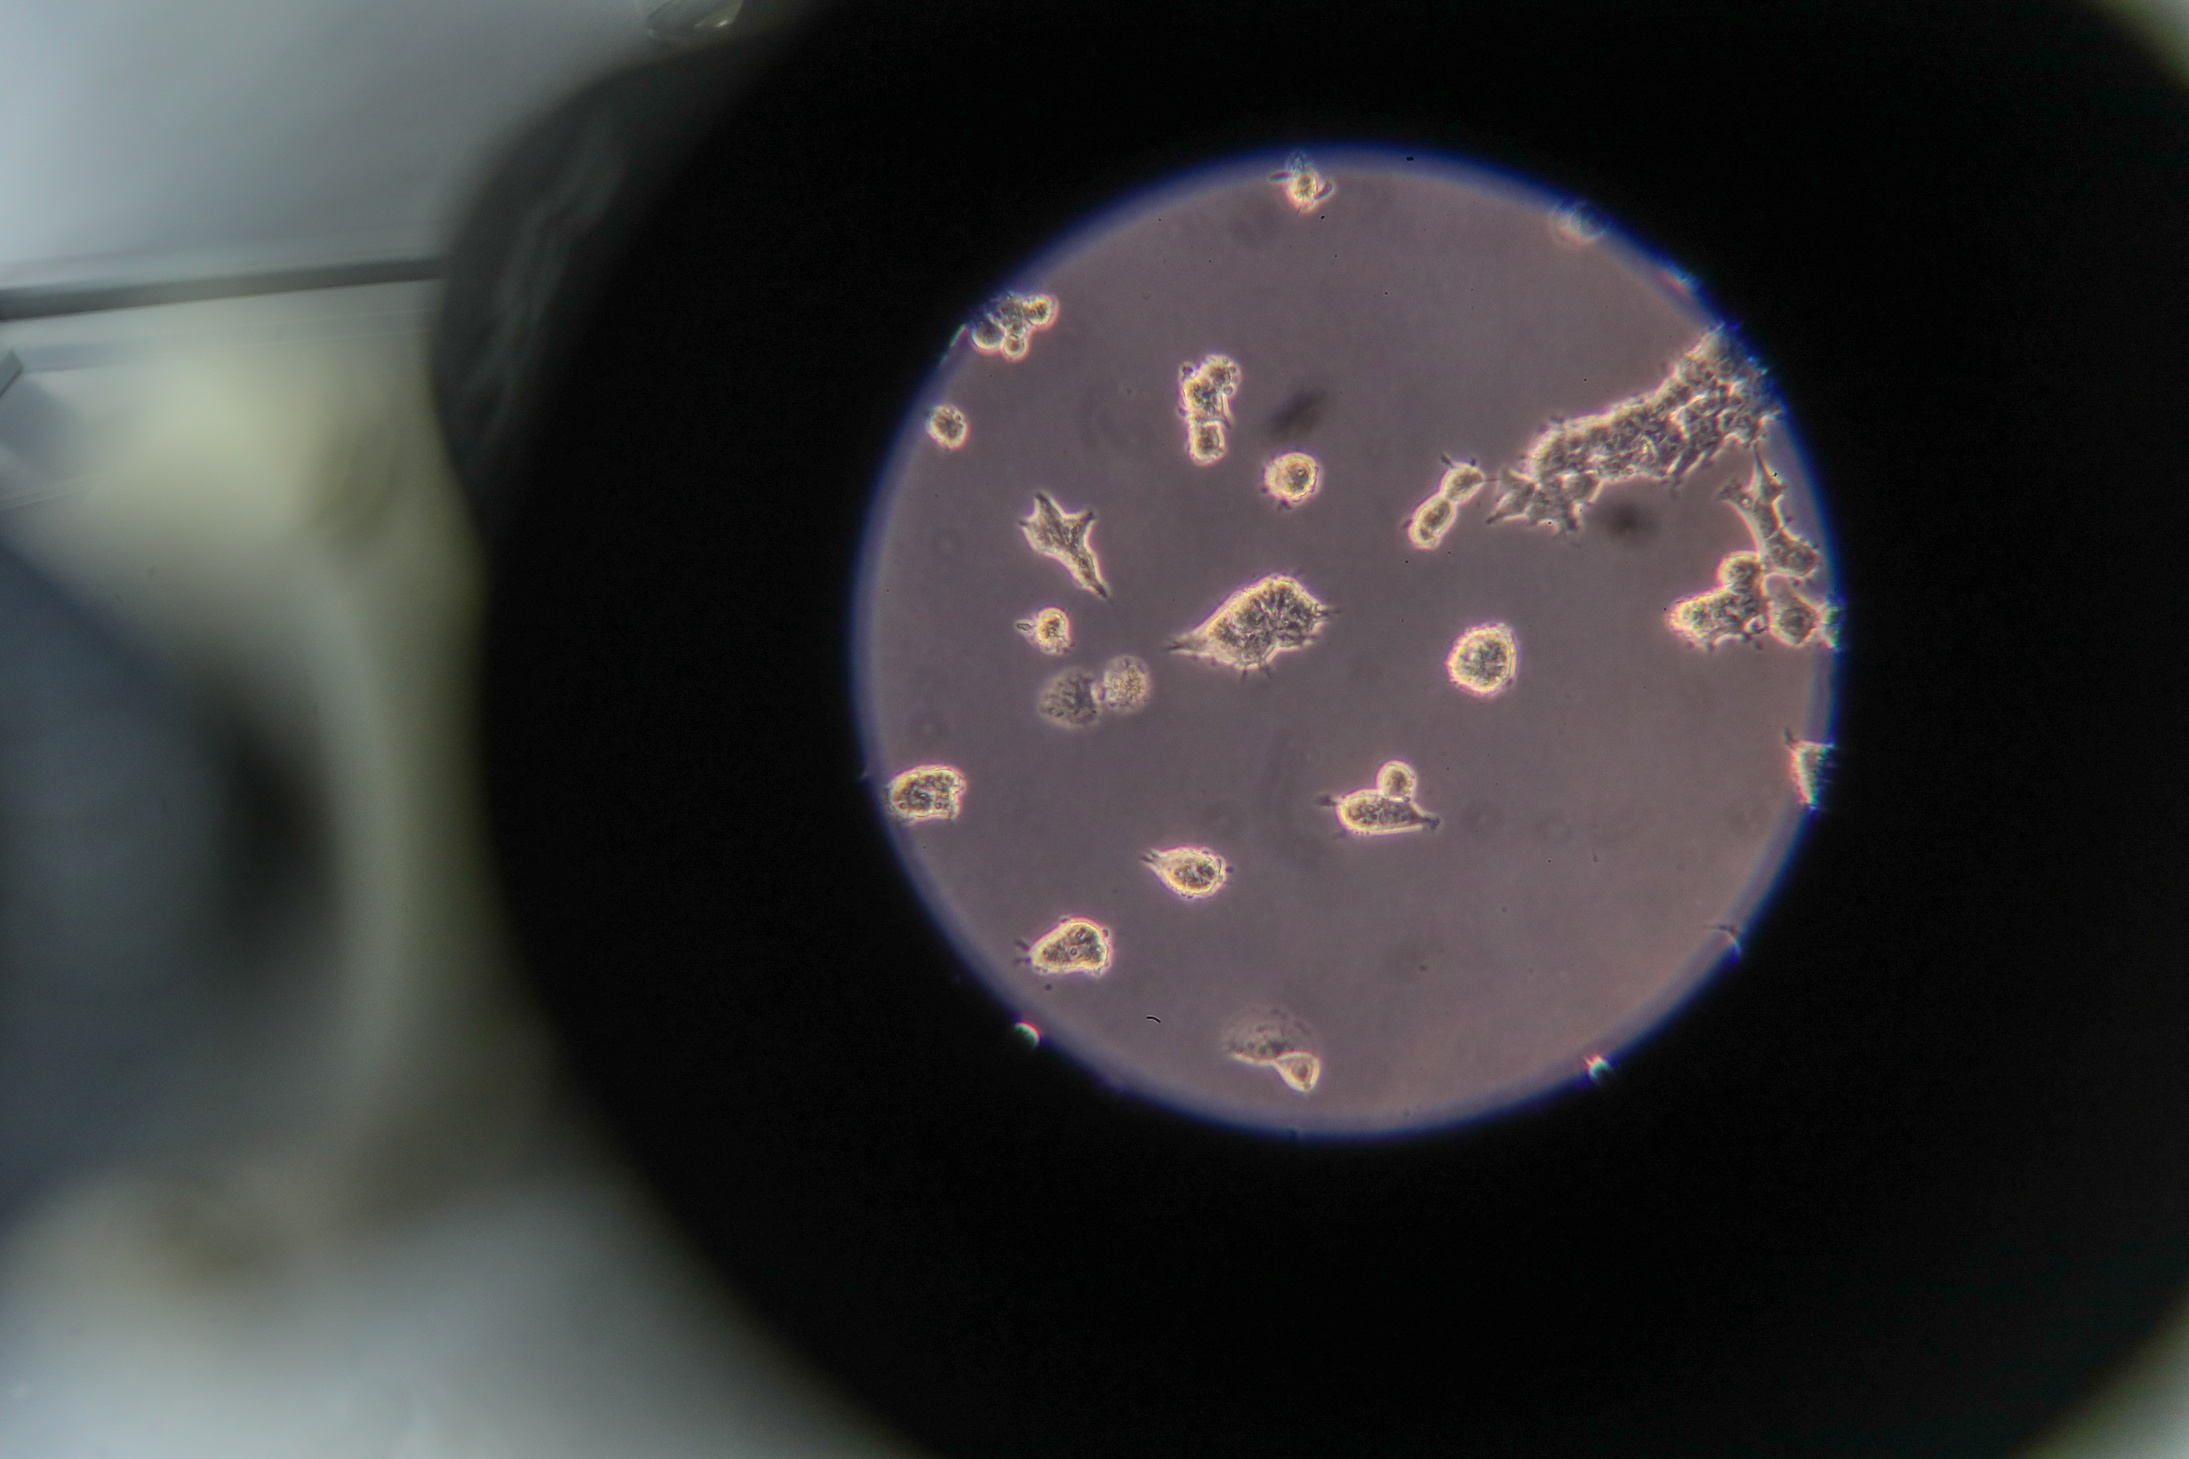

People with high COVID-19 antibody levels may have disease with no symptoms, expert says

MOSCOW, March 1. /TASS/. People having high levels of COVID-19 antibodies may have the disease with no symptoms, Alexei Mazus, a visiting HIV specialist of the Russian Health Ministry and Moscow’s public health department, said on Monday.